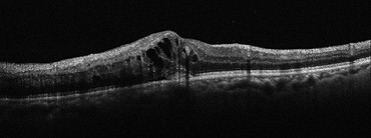

加齢黄斑変性

萎縮型は、加齢の影響で黄斑組織が委縮してしまいます。特徴としては、進行がとてもゆっくりで、急激な視力低下をもたらさないということが挙げられます。経過観察が重要になります。

滲出型は、新生血管というもろい血管が生えてきます。血管が破れて出血や、血液中の水分がもれて、黄斑部に浮腫が生じ、障害を起こします。日本人の加齢黄斑変性の患者様の多くはこの滲出型と言われています。症状の進行が早く、著しい視力低下がみられるので、早期診断・早期治療が重要になります。

治療としては、萎縮型の多くは特別な治療を必要とすることはなく、経過観察が重要となります。一方、滲出型は、新生血管を抑制する抗VEGD療法や光凝固術による治療を必要とすることがあります。当院では、必要に応じて連携する医療機関をご紹介しております。